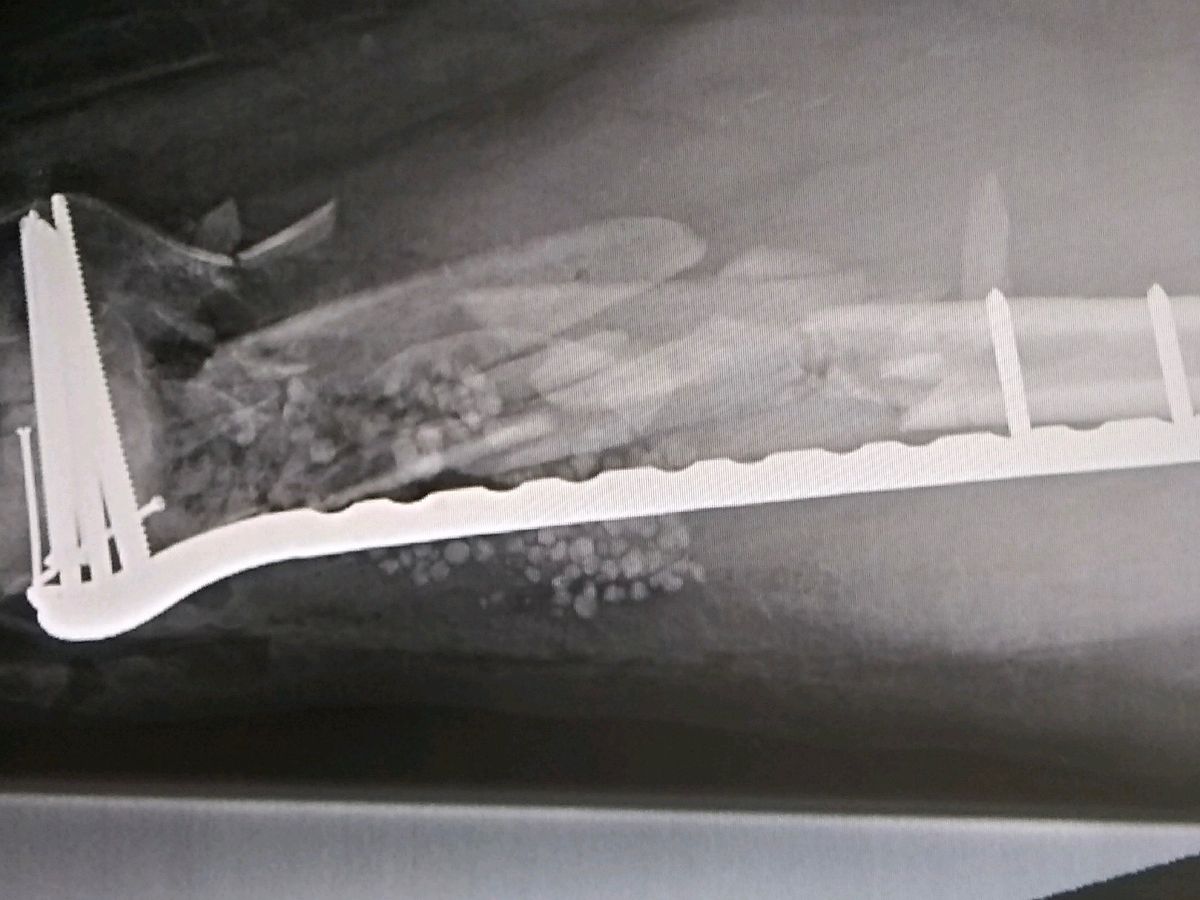

11/2 Update! So Al had his post op 2 week visit, surgeon said he has bone splinters and you can totally see the mess that is his leg in his x rays so Al is not arguing, but he is unhappy about being stuck in a rehab facility in Sacramento still. He will be there for awhile longer in case any of those splinters start moving or anything else goes wrong. It’s pretty technical stuff and our hospitals can’t handle it. So your donations are critical and thank you! He can’t do much from the hospital bed or wheelchair in Sacramento. Looks like a few more weeks to a month before he can possibly return home. They say there’s a 70% chance he won’t need a bone graft surgery so fingers crossed.

He was life flighted to Sacramento UCDavis and they managed to save his leg, but it’s going to be months of wheelchairs and a very hard road, unable to work or even drive. He’s got a broken right ankle and left femur that’s being plated together (it was poking out of his leg), hopefully won’t need a bone graft… and many other more minor injuries. You all know Al has a heart of gold and he’d do it for you. Donate if you can. Help him pay his bills for a couple months at least so he can get back on two wheels! Thank you.